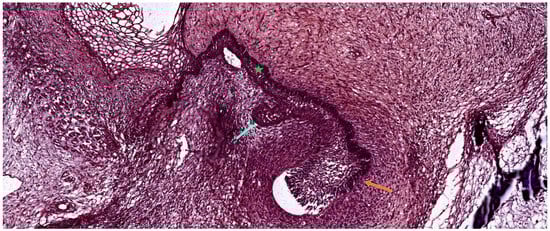

3.3. The Bell Stage

3.3.1. Early Bell Stage